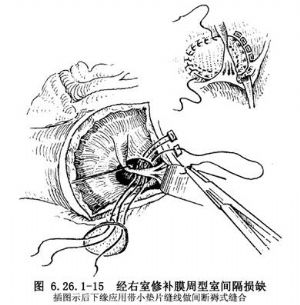

①膜周型缺損修補法:將深拉鉤經右室切口伸入三尖瓣隔瓣下方將隔瓣及圓錐乳頭肌向上牽拉,先於缺損後下緣應用3-0帶小墊片雙頭無創縫線做間斷褥式縫合,從圓錐乳頭肌止點後方開始距肌肉緣5mm的間隔右室面進針,順時針方向縫合(圖6.26.1-15),做3~4個褥式縫合後,縫線即可由肌肉緣轉移到三尖瓣隔瓣根部,此處所有縫線均需置於腱索下方,縫到三尖瓣隔瓣與前瓣交界部位後,褥式縫線再轉移到三尖瓣前葉根部和心室漏斗褶或主動脈瓣環上,然後繼續沿心室漏斗褶縫合,在鄰近冠狀動脈無冠瓣時必須看清主動脈瓣再下針,而且縫線穿過肌肉應有足夠深度,縫線分別穿過補片,將補片送下後結紮,剩下的室間隔缺損上緣和前緣均爲漏斗隔及隔束形成的肌肉緣,可進行連續縫合,縫線必須穿過肌肉緣的全層,直到與圓錐乳頭肌止點後方的縫線匯合再結紮,缺損全部閉合(圖6.26.1-15右上插圖)。